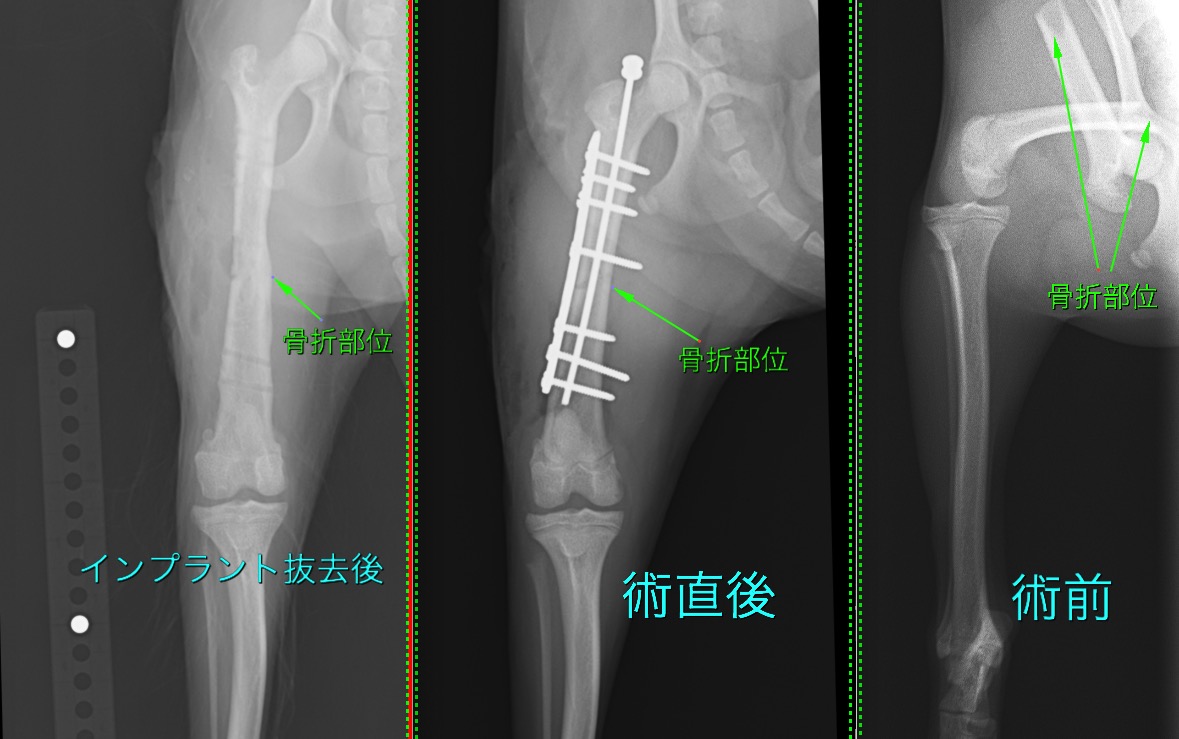

大腿骨骨幹部骨折の小型犬の1例(整形外科、骨折手術、後ろ足、プレート、ピン)

強い衝撃により大腿骨(後ろ足のももの骨)を骨折してしまったわんちゃんです。

髄内ピンとプレートによる”プレートロッド法”により整復しました。

術後1か月後から段階的にインプラントを間引き、術後2か月半ですべてのインプラントを抜去しました。